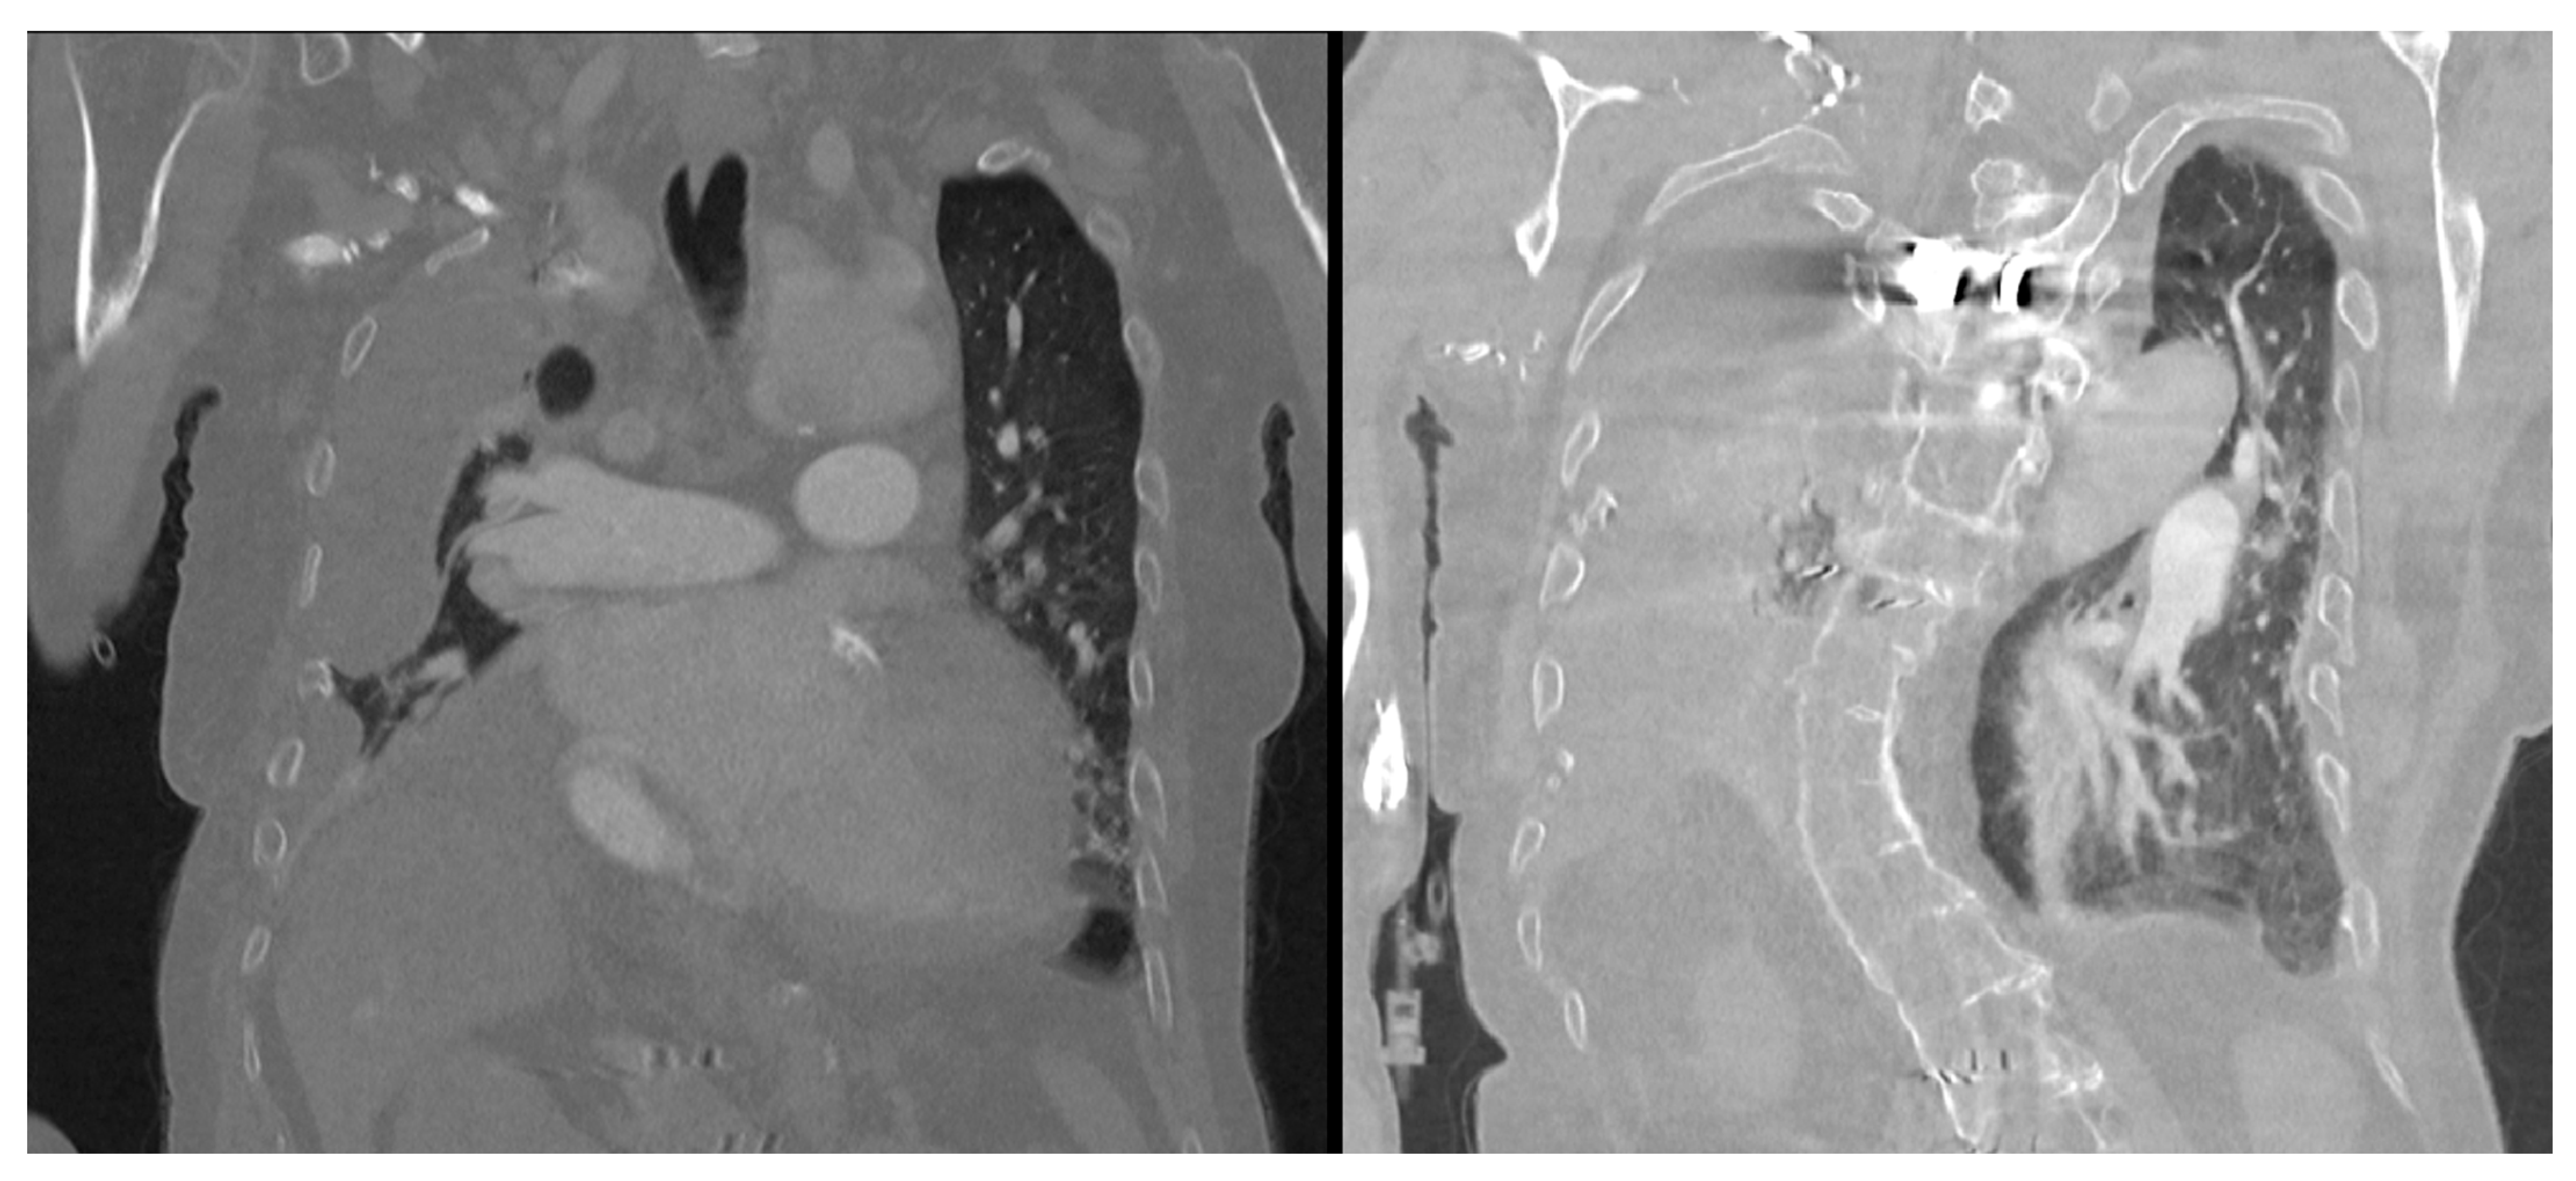

Figure 2). A chest CT scan showed scoliosis, postoperative metallic artefacts from prior spinal surgery, and dilatation of the right heart chambers (

Figure 3).